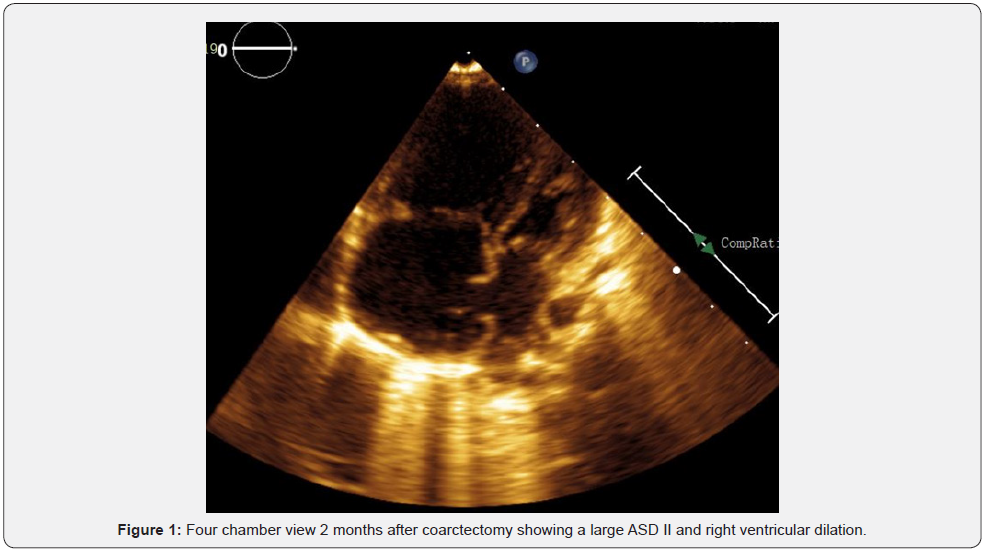

What was noticed on the postoperative echo was that the atrial septal defect type ostium secundum was quite large (Figure 1), with significant left-to right shunting and with marked right ventricular dilation (Figure 2). The left ventricle was hypertrophic, with reversed E/A ratio of the flow through the mitral valve. The left ventricle appeared small in relation to the markedly dilated right ventricle, but the left ventricular size was normal for the weight and the height of the patient.